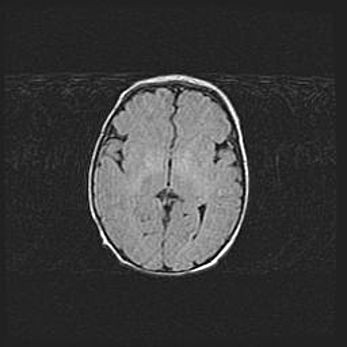

Открытая гидроцефалия.

Возраст: 9 месяцев 12 дней

Вес: 6800 г

Пол: мужской

Окружность головы: 41,5 см

Срок гестации: 28 недель

Гидроцефалия головного мозга у новорожденных имеет характерный признак: опережающий рост окружности головы приводит к визуально хорошо определяемой гидроцефальной форме сильно увеличенного в объёме черепа. Детские неврологи определяют следующие симптомы гидроцефалии у грудничков: выбухающий напряжённый родничок, частое запрокидывание головы, смещение глазных яблок к низу.